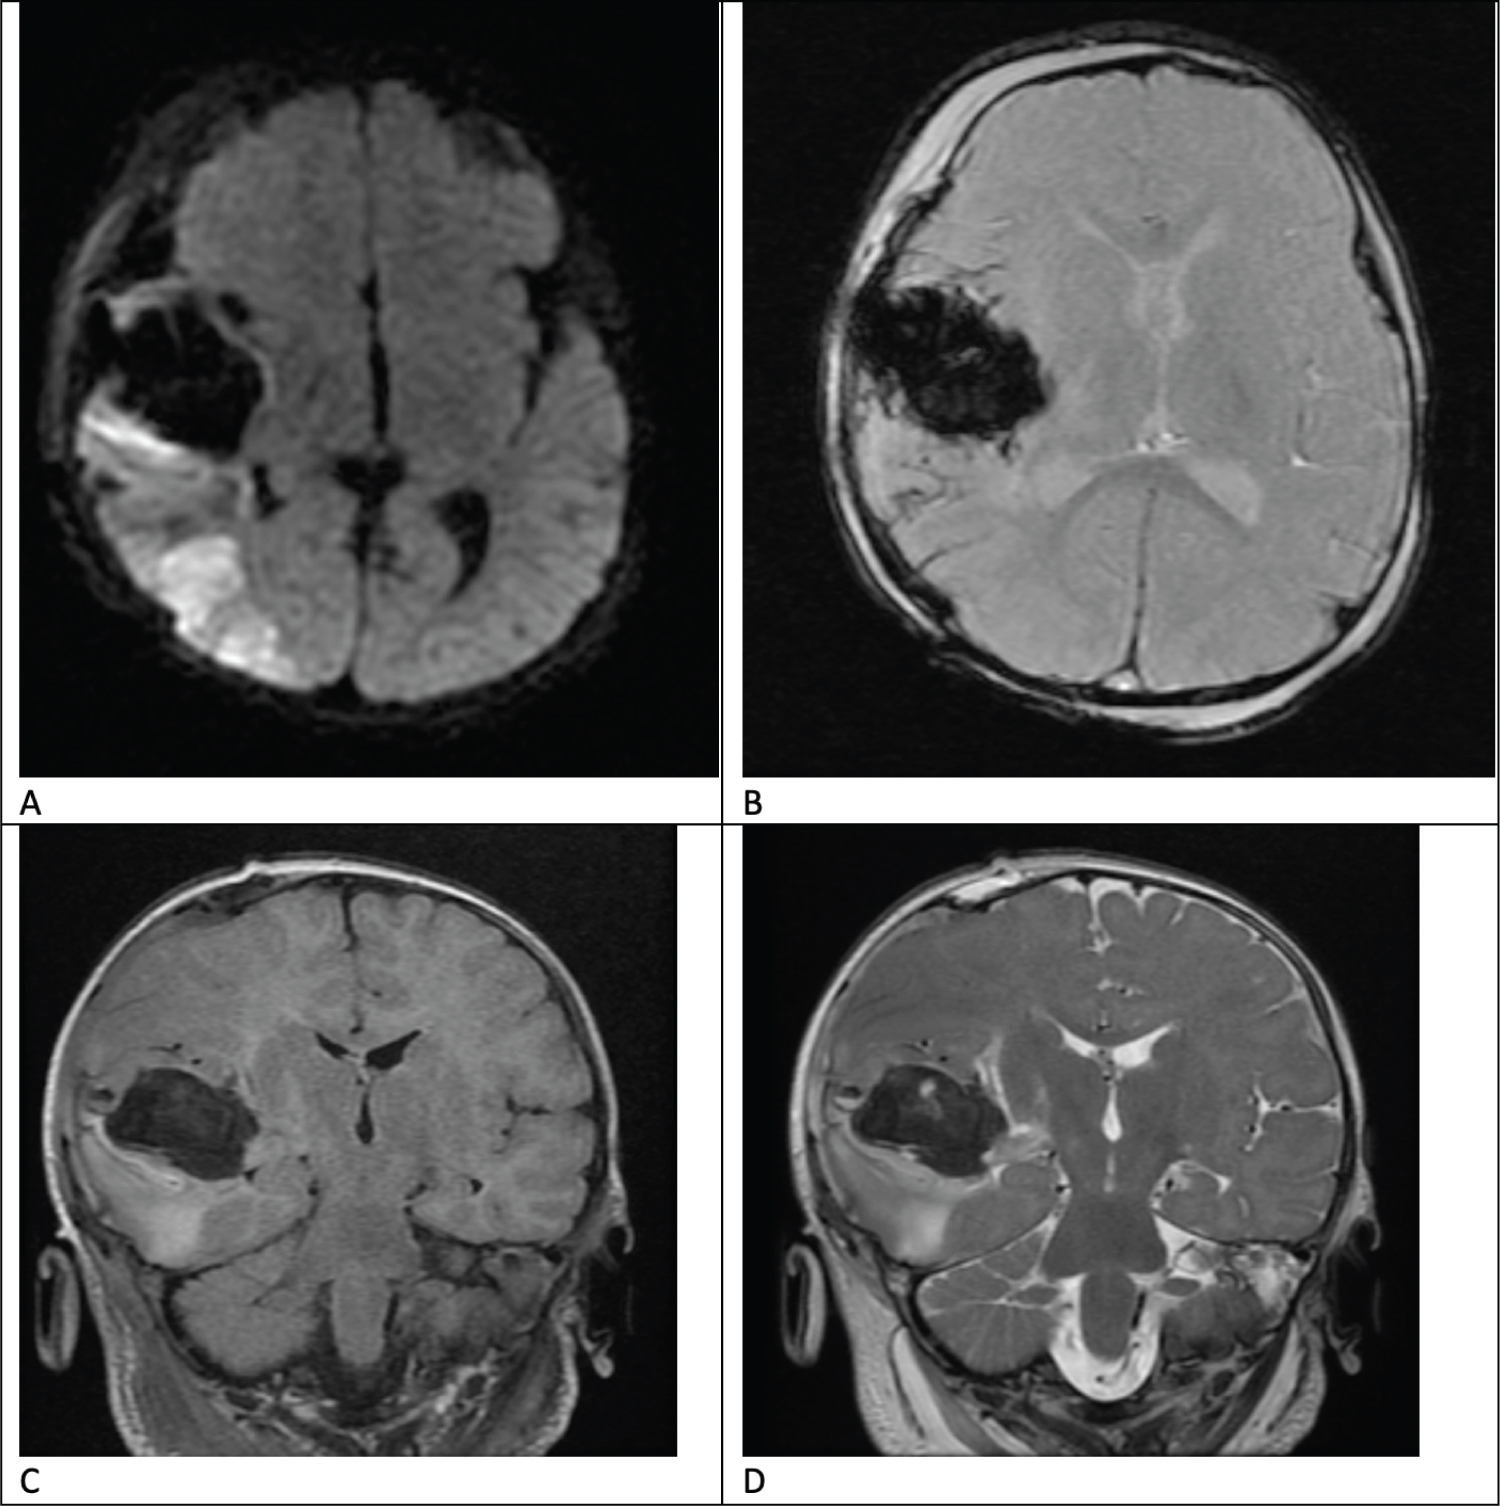

Although an MRI on POD 2 demonstrated ischemia of the right middle cerebral artery (MCA) territory (Figure 5), gray-white matter differentiation was largely preserved. He demonstrated neurological improvement over the following two weeks; on POD 9, the patient was successfully extubated, and he was awake and alert, opening eyes spontaneously, tracking, and moving all four extremities with greater activity on the right side than the left.

Figure 5: Post-operative Magnetic Resonance Imaging (MRI) demonstrating ischemia of the right middle cerebral artery territory and residual hematoma with improved mid-line shift on various sequences. A) Axial Diffusion Weighted Image, B) Axial Gradient Recalled Echo (GRE), C) Coronal T2 Flair sequence, D) Coronal T2 Fast Spin Echo (FSE). View Figure 5